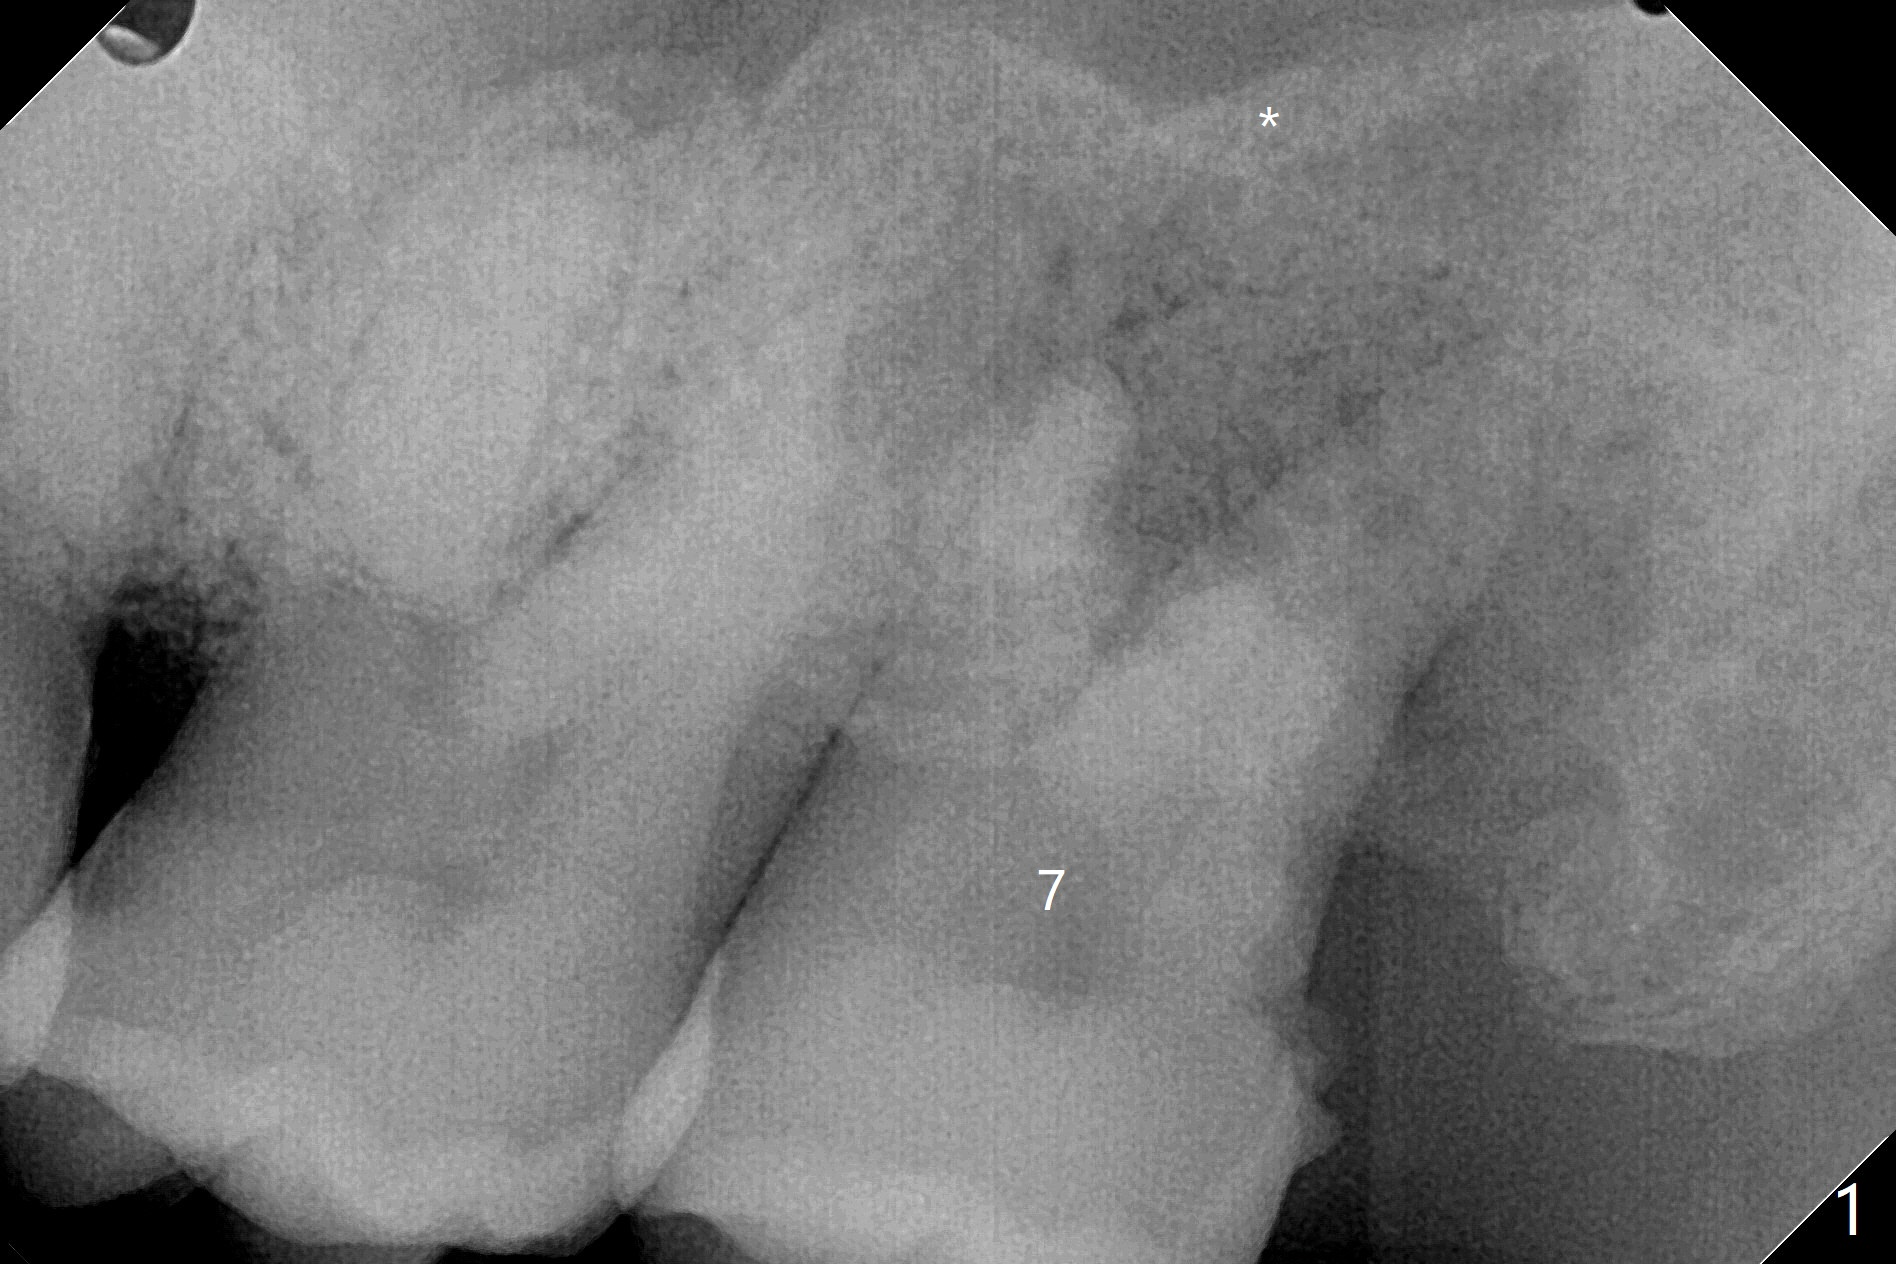

53岁黑男要求拔除松动,剧烈疼痛的左上7(图一(*:上颌窦底板)),同意植骨,分期付款。拔牙后牙槽窝硕大,有许多难以刮除的肉芽组织,出血多,颊侧骨壁应该缺失。在放置GEM21S人工合成骨和异体骨(主要部分)前,在牙槽窝深部放置两个Osteogen塞(图二:P,止血,所谓胶原骨,另外一种人工合成骨),覆盖不可吸收膜,PTFE缝线,间隙保持器,牙周敷料。由于对合牙是智齿,垂直高度有限,放置保持器和敷料有困难。去除炎性肉芽组织,使用两个大小不太带齿刮匙,血管钳,特殊镊子以及带金刚石镊子(图三),反复多次使用自配生理盐水(图四)冲洗。